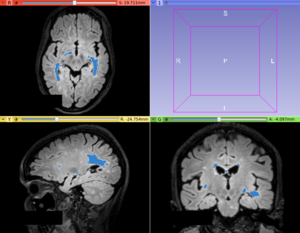

This module offers a hybrid algorithm based on the iterative contrast enhancement (ICE) and logistic classification methods for hyperintense Multiple Sclerosis lesion segmentation task.

• Use Case 1: Hyperintense Multiple Sclerosis (MS) lesions segmentation

• Hyperintense MS lesions, mainly in T2-FLAIR images, have an easy application of this lesion segmentation procedure

• Minimum Lesion Size

• Set the minimum lesion size adopted as a true lesion in the final lesion map. Units are given in number of voxels